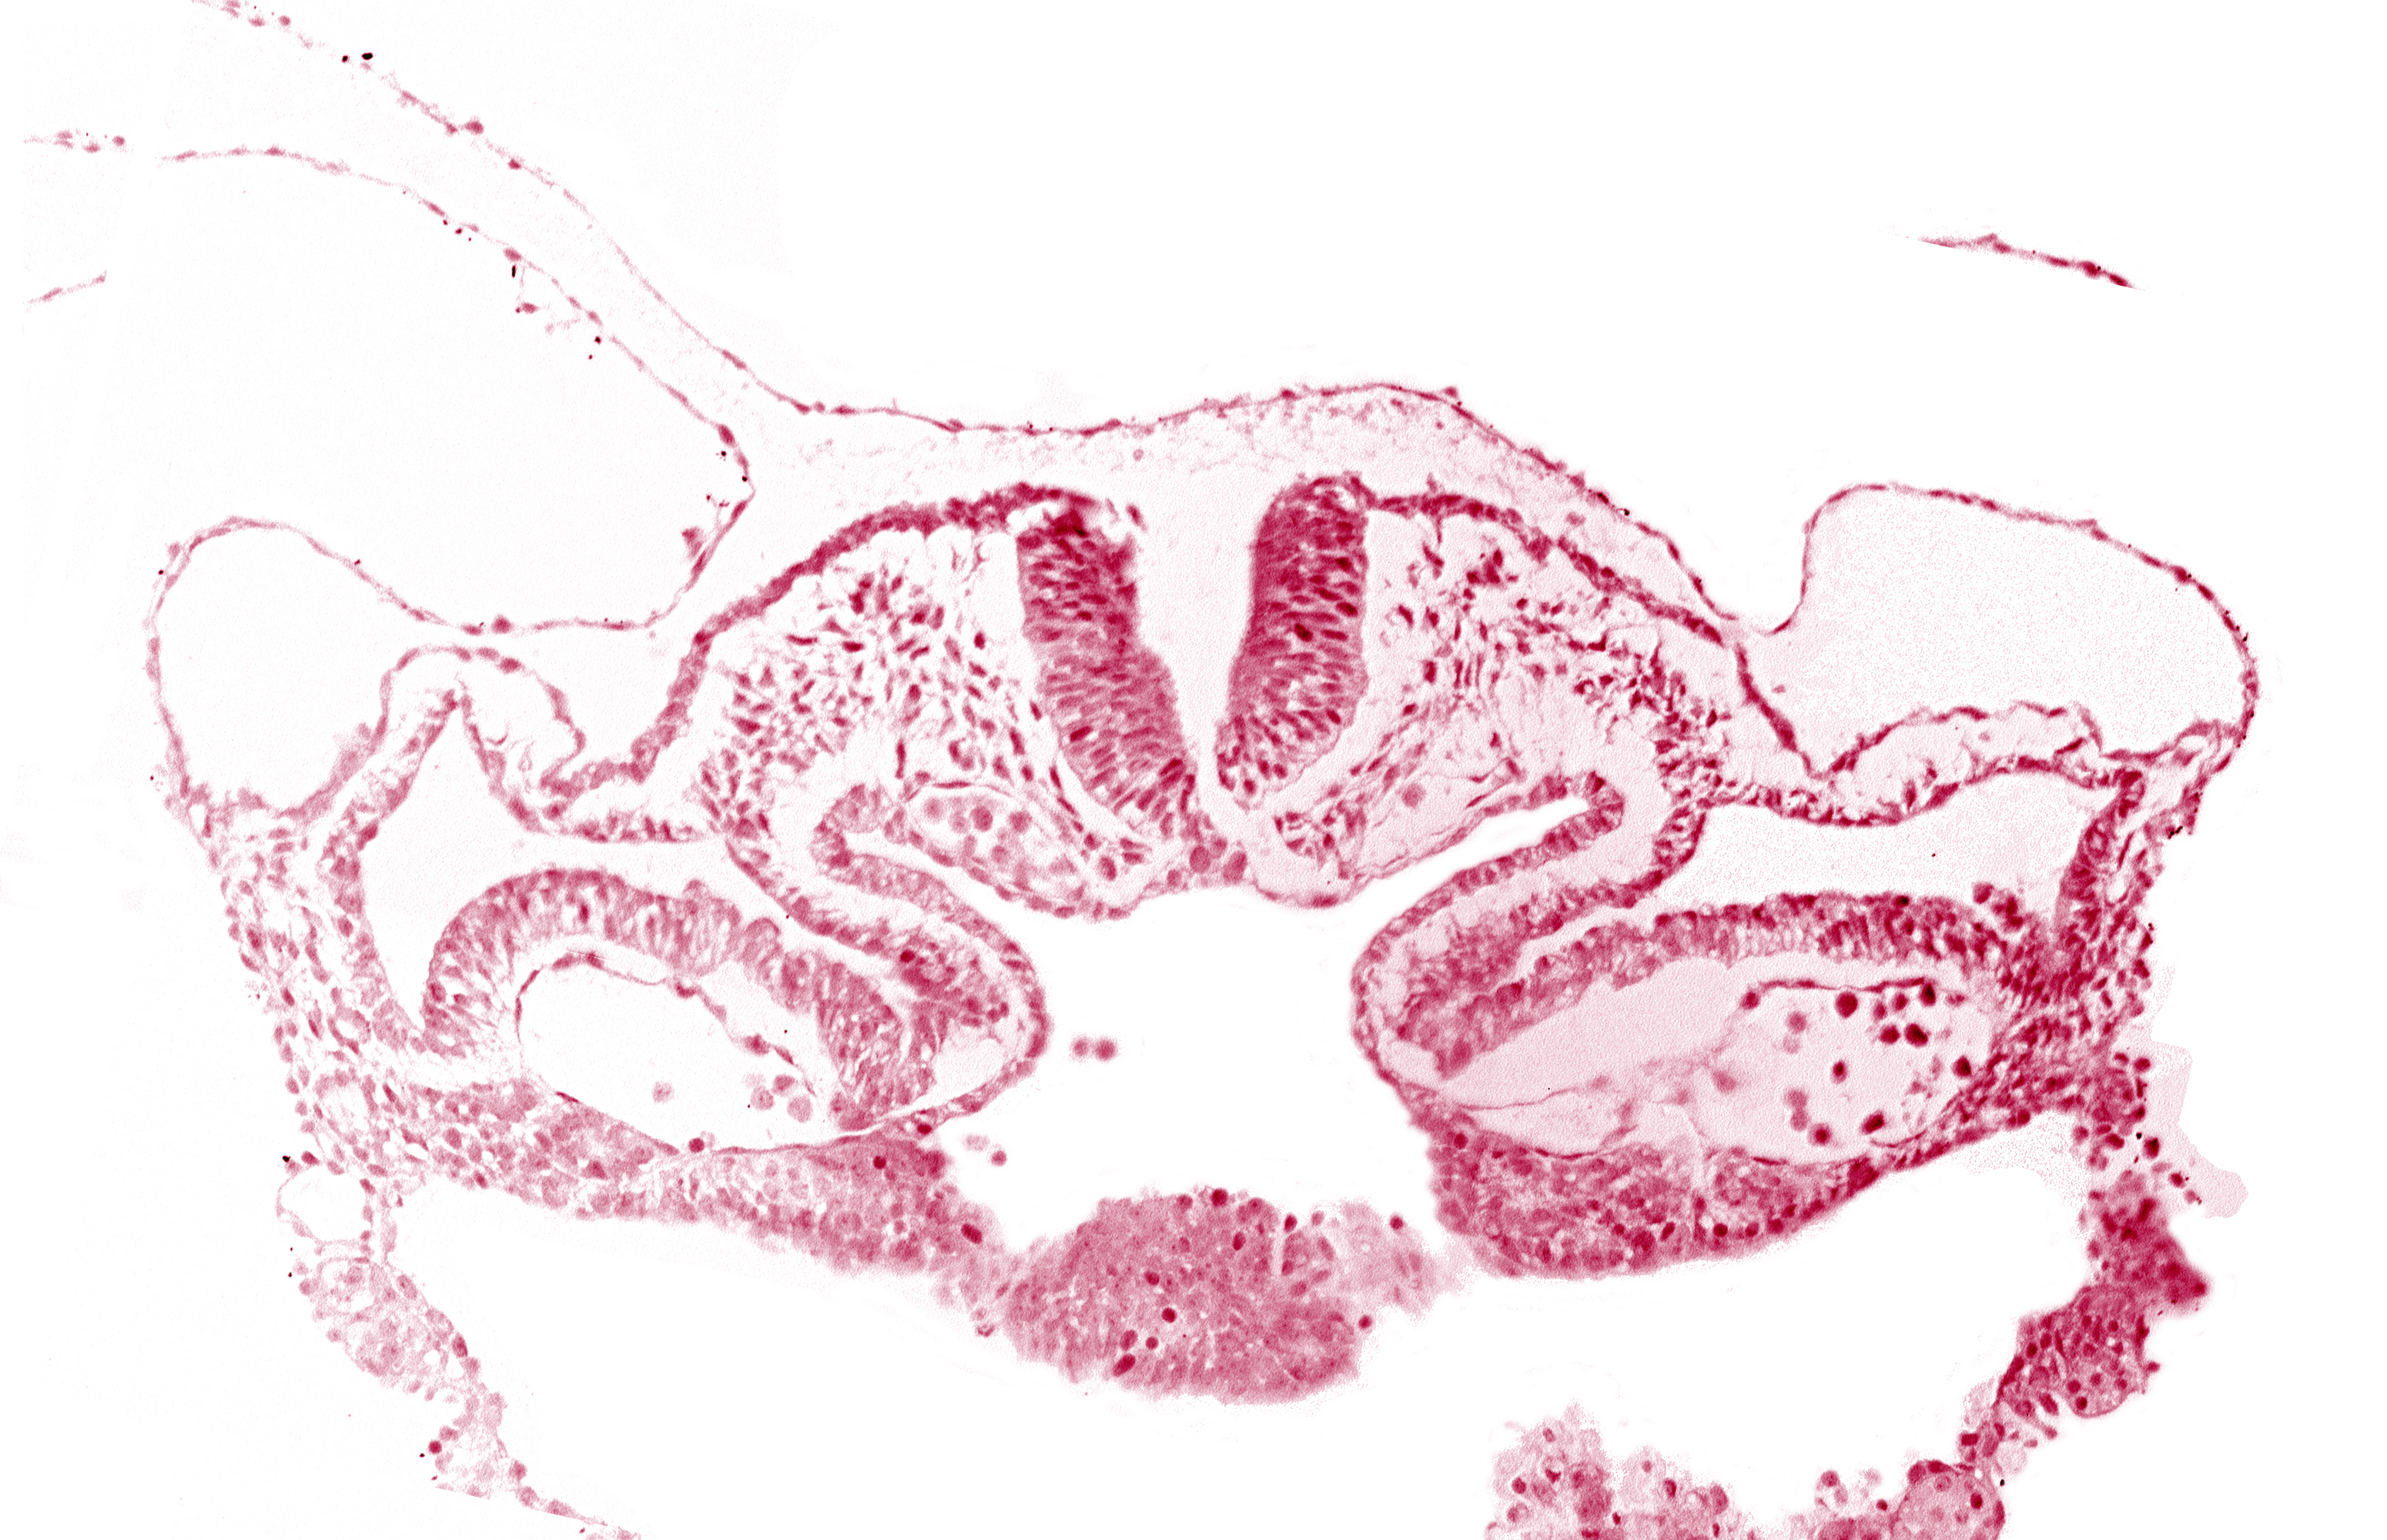

Carnegie Embryo #6330 | Location: 01-10-11

Keywords: alar plate(s), basal plate, cephalic intestinal portal, dorsal aorta, head mesenchyme, hepatic plate / septum transversum region, neural fold [rhombencephalon (Rh. C)], notochordal plate, presumptive left atrium, presumptive right atrium, primordial pericardioperitoneal canal (pleural cavity), sulcus limitans

Source: The Virtual Human Embryo.